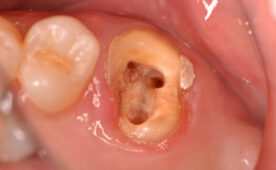

60代女性。3年前に他院にて自費治療で入れたセラミックの詰め物が…